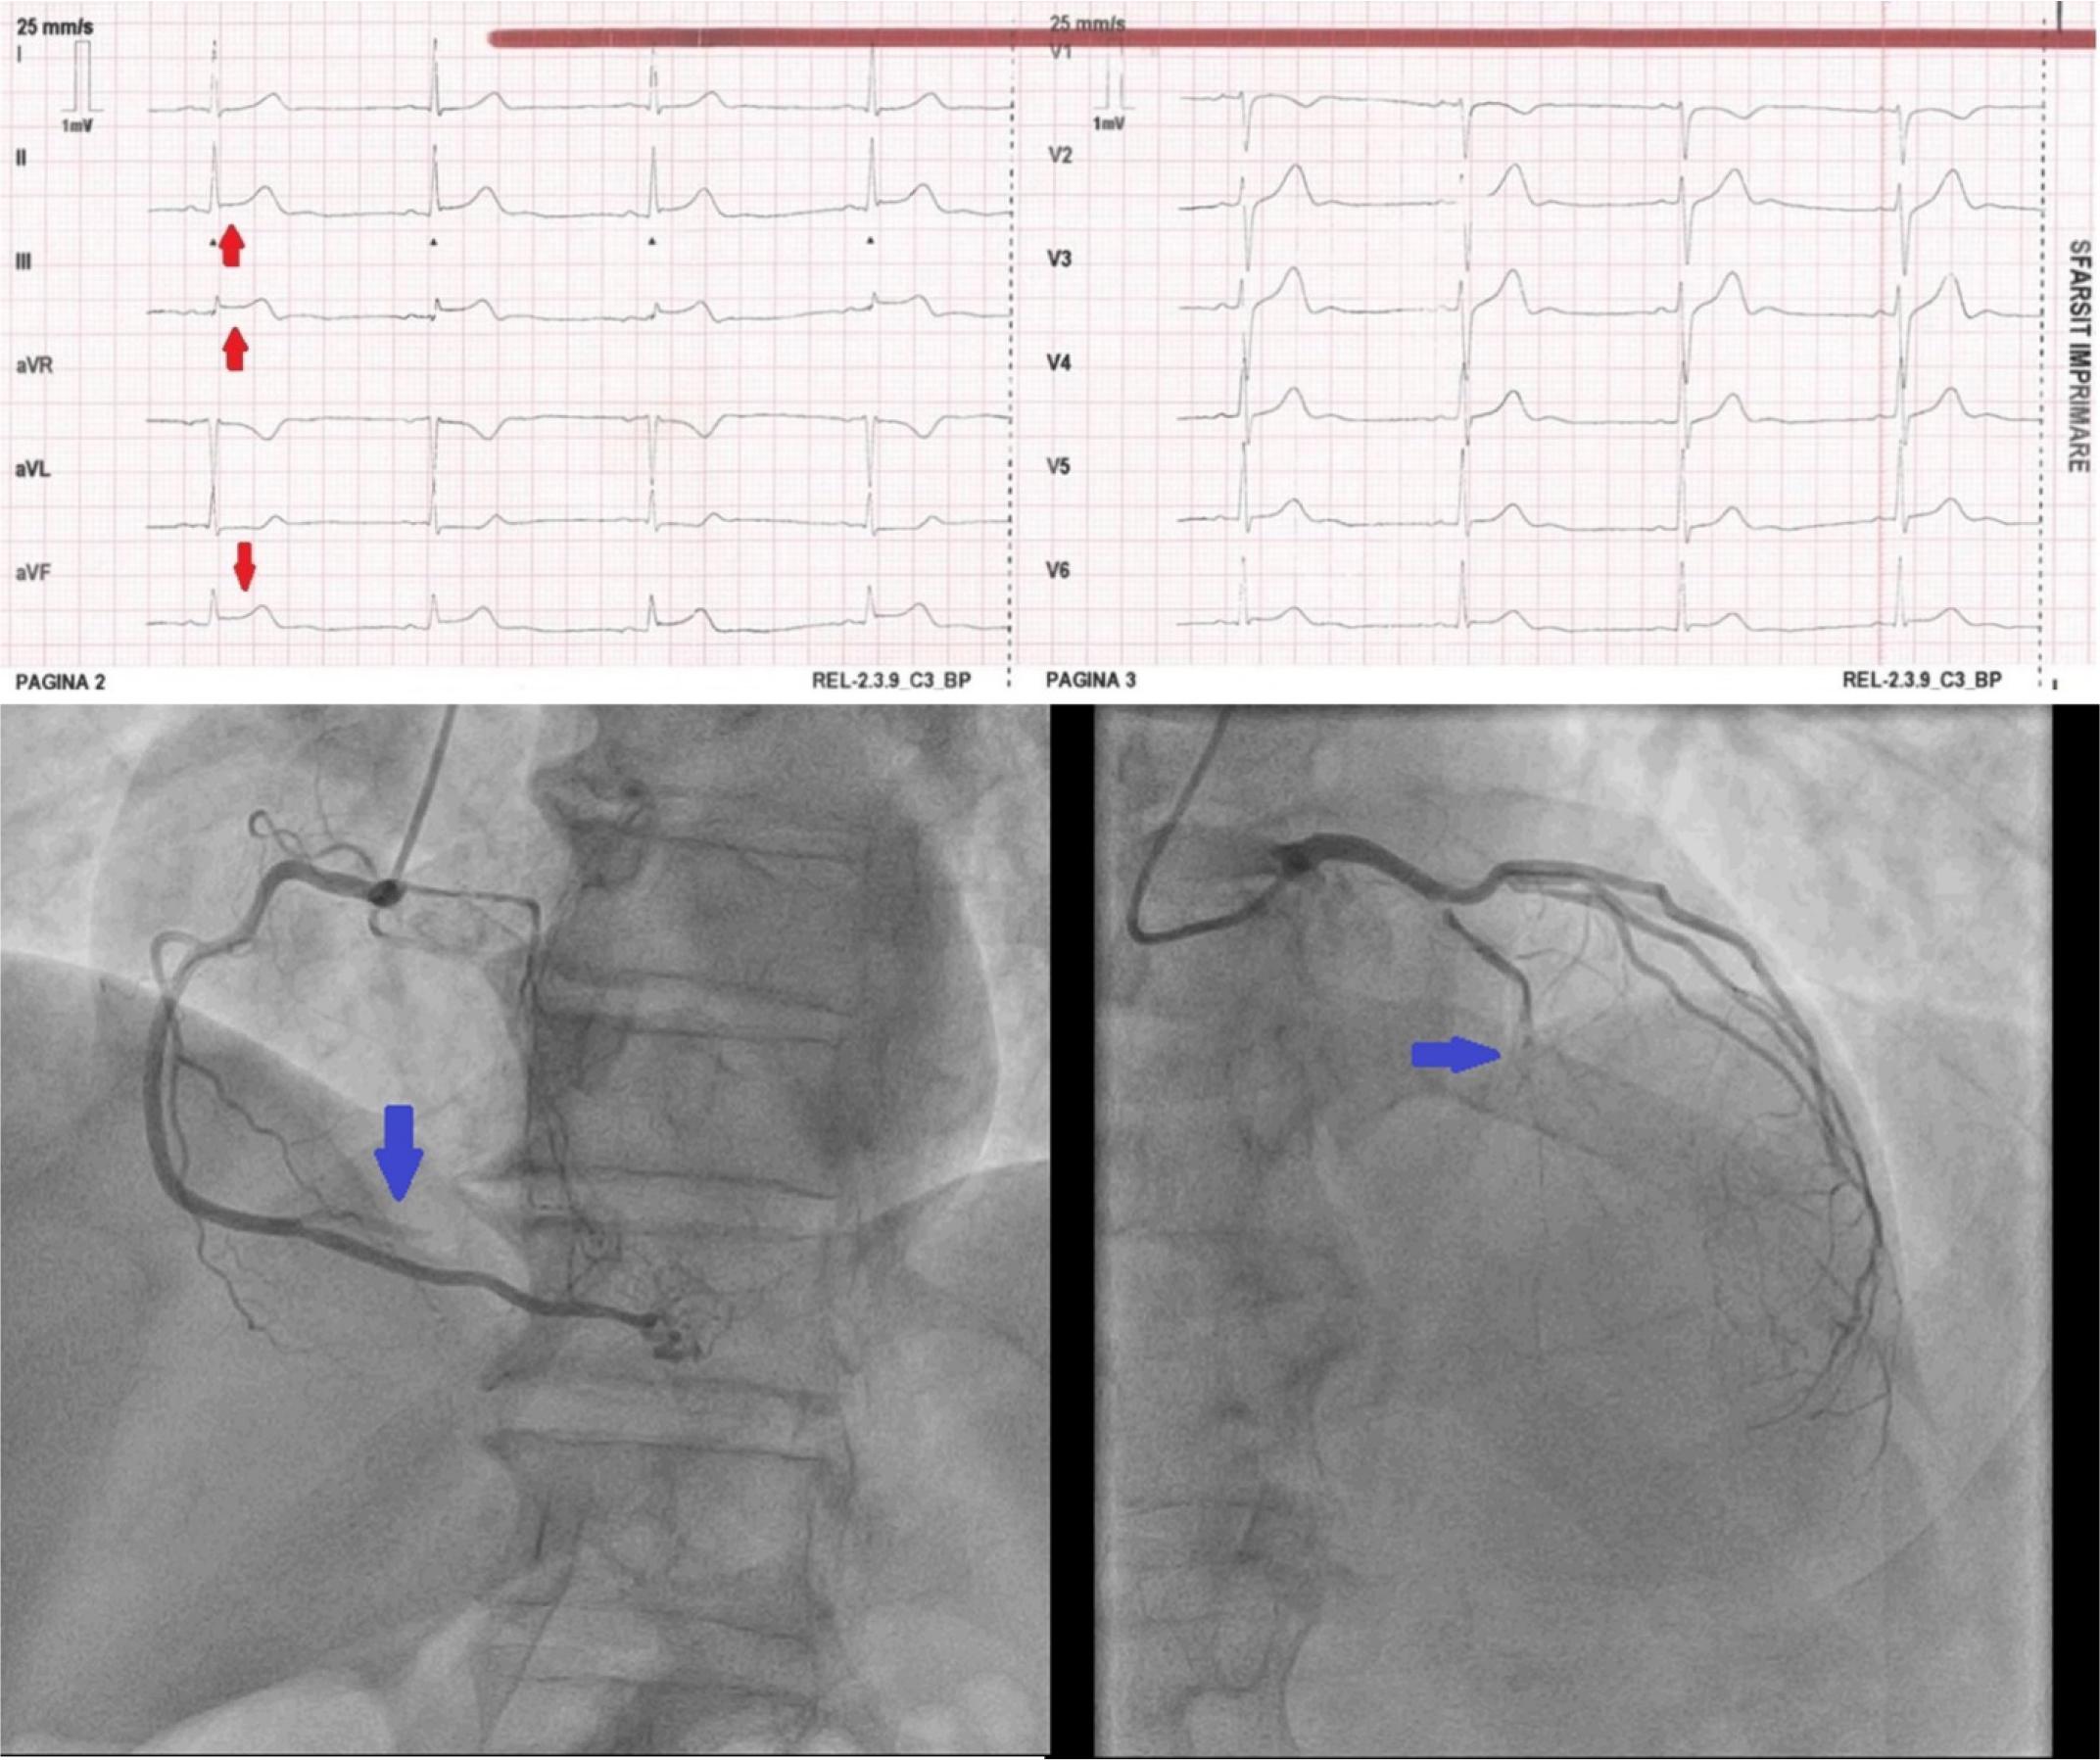

Figure 2